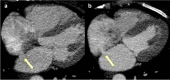

Results: Chronic animal studies (n = 9) were carried out to 30- and 60-day time points and exhibited sustained shunt patency with histology demonstrating completely healed margins, endothelialization, and no trauma to adjacent atrial tissue. Preliminary clinical safety and feasibility were validated in a first-in-human study in patients with heart failure with preserved ejection fraction (n = 15). All patients demonstrated shunt patency by transesophageal echocardiographic imaging at 1, 3, and 6 months, as well as cardiac computed tomography imaging at 6-month follow-up timepoints.